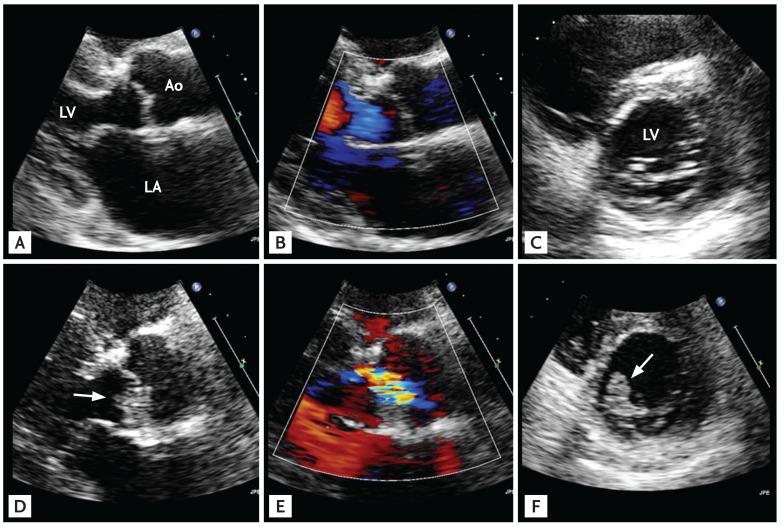

Figure 4

Representative echocardiographic images of a patient with community-acquired infective endocarditis involving an apparently normal-looking valve. The patient, a 66-year-old female with poorly controlled diabetes mellitus, visited the emergency department due to fever and back pain. Blood culture showed Enterococcus faecalis bacteremia. Transthoracic echocardiographic images showed a normal-appearing mitral valve with a suspicious mass attached to the left atrial side of the mitral leaflet (A, B) and transesophageal echocardiography clearly showed a textured surface typical of vegetation (C, D; arrows). Ao, aorta; LA, left atrium; LV, left ventricle.